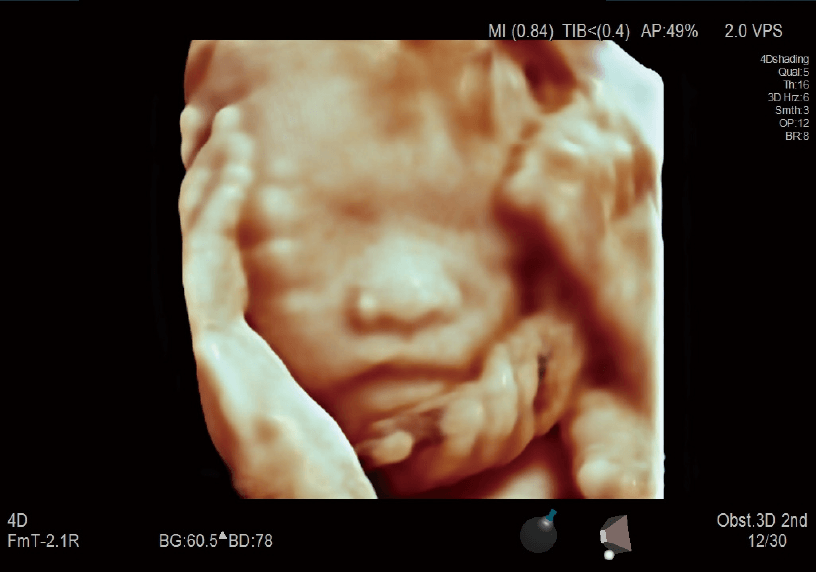

4Dshading (4D gölgeleme) / 4Dtranslucence (4D yarısaydamlık)

4Dshading (4B gölgeleme), bir ışık veriliyormuş gibi gerçekçi bir doğal gölgelemeyi yansıtmak için kullanılan bir moddur. 4Dtranslucence, doku sınırlarını ayıklar ve beyin, sindirim kanalı ve benzerlerinin kavite içi yapılarının görüntülenmesini sağlamak için bunları üst üste bindirir.